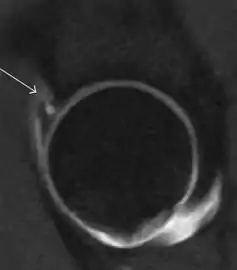

Synovial chondromatosis can be confidently diagnosed by X-ray when calcified cartilaginous chondromas are seen. However, other synovial proliferative processes, such as pigmented villonodular synovitis, require MRI for accurate diagnosis, although noncalcified synovitis can be suspected in radiographs by indirect signs, such as soft tissue swelling and/or erosions in the femoral head, femoral neck, or acetabulum (Figure 7).[1]

Figure 7:

Axial CT image of pigmented villonodular synovitis eroding the posterior cortex of the femoral neck.[1]

Sagittal T2* gradient echo image showing a posterior soft tissue mass with hypointense areas secondary to hemosiderin deposition.[1]

In synovial proliferative disorders, MRI demonstrates synovial hypertrophy. In the case of PVNS, characteristic foci of low signal intensity related to hemosiderin deposition are better seen on gradient echo T2* images (Figure 7). In the case of synovial osteochondromatosis, the synovial hypertrophy is accompanied by intermediate signal cartilaginous loose bodies and/or low signal calcified loose bodies.[1]